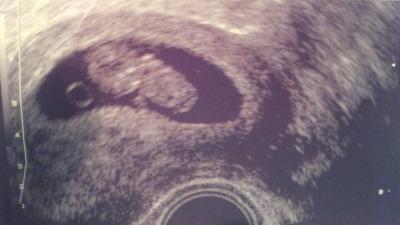

Hallo zusammen, ich hatte gestern auch einen FA-Termin und es sieht soweit alles gut aus. Das Kleine hatte eine SSL von 27. War damit 1-2 Tage zurück. Was mache jetzt schon wieder verunsichert. Aber der FA meinte, dass dies durch Messfehler schnell passieren kann. Naja, letztlich hilft ja leider sowieso nur, weiter abzuwarten. Ich darf auch in 2 Wochen dann in der 12. SSW nochmal wieder kommen und hoffe, dass dann alles in Ordnung ist weiterhin und ich etwas beruhigter an die Sache rangehen kann. Liebe Grüße Ella

Bild zu FA-Besuch gestern - Forum für Oktober - Mamis